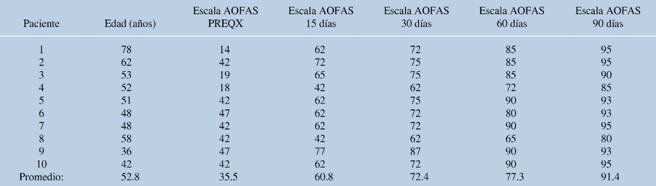

La corrección media del ángulo intermetatarsiano fue de 8.8 grados y la del ángulo metatarsofalángico, de 9.12 grados (inicial de 15 y 36.87 grados, respectivamente) (Tablas 2 y 3). Se presentó una complicación transoperatoria, con fractura diafisaria del segundo metatarsiano que se resolvió en el mismo evento mediante fijación con clavo Kirschner 1.6 mm. El análisis estadístico mostró una correlación inversamente proporcional de la corrección del ángulo intermetatarsiano y el puntaje de la escala AOFAS (p = 0.02).

Tabla 2: Resultados de la valoración del ángulo intermetatarsiano de acuerdo al tiempo de evolución.

Ángulo IMT = ángulo intermetatarsiano; PREQX = previo al tratamiento quirúrgico.